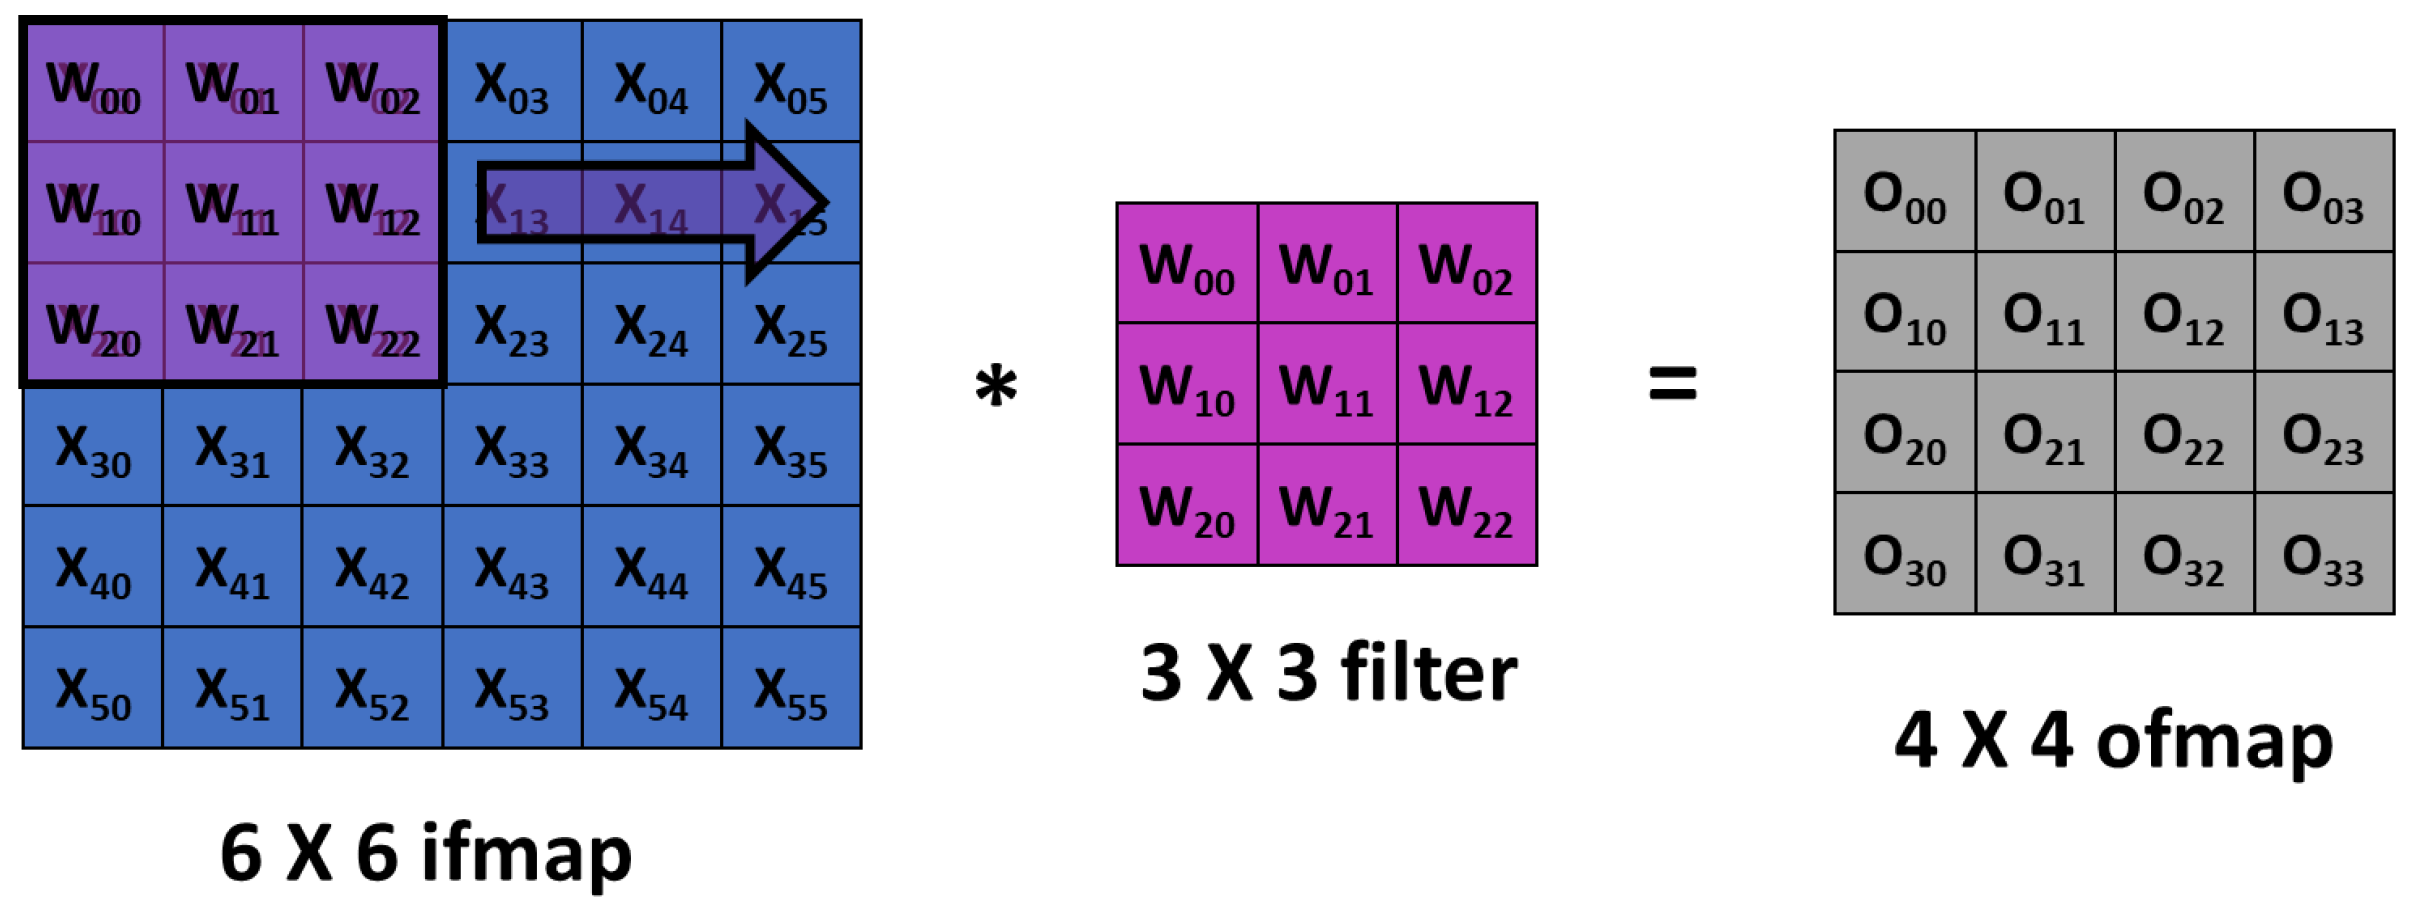

Convolutional Neural Networks (CNNs) showed excellent performance in understanding the hidden features of images, and hence, received significant attention from diverse fields, including healthcare. CNN is designed to adaptively and automatically acquire spatial hierarchies of features, from low- to high-level patterns. One important characteristics of CNN is that it does not require manual feature extraction. A typical architecture of CNN consists of multiple blocks with three kinds of layers: convolution, pooling, and fully connected layers. Feature extraction is performed by the convolution layer, which has convolution and nonlinear activation operations. The input image is divided into small segments called tensors. A feature map is obtained by the element-wise product of kernel and tensor. Different number of feature maps can be obtained by using multiple kernels. A convolution operation allows weight sharing across the input image, which enables the extraction of different features with the same weights, and thus, reduces the total number of parameters as shown in

Figure 1. Output feature map (ofmap) is generated by multiplication of input feature map (ifmap) values (X) by weights (W) in the filter window and addition of the results generated from the multiplications. The convolution layers can be characterized by diverse parameters such as the number of kernels, kernel size, and padding. These parameters are set before the training process and kernel weights are learned during the training. The result of convolution is given to a nonlinear function such as a ReLU (Rectified Linear Unit). A good activation function usually speeds up the learning process.